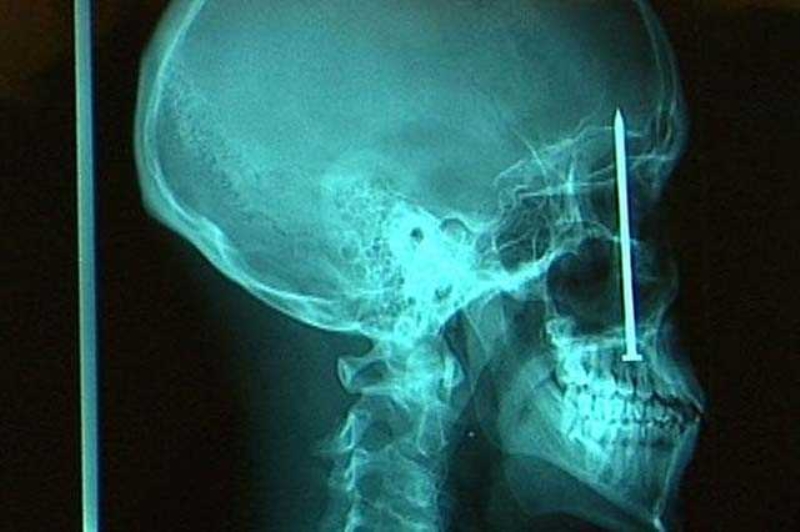

KAFADA BİR ÇİVİ

Bir inşaat işçisi bir gün doktora gitti. Dişi ağrıyan ve bulanık gördüğünü söyleyen adamın sorunu ise 20 yaş dişi değildi. Kafatasında bir çivi bulunan adam, bir hafta önce çivi makinesi ile çalışırken bir sorun yaşamıştı. makine tepmiş, adamın ağzından içeri bir çivi göndermiş ve bu çivi kafatasına kadar gitmişti!